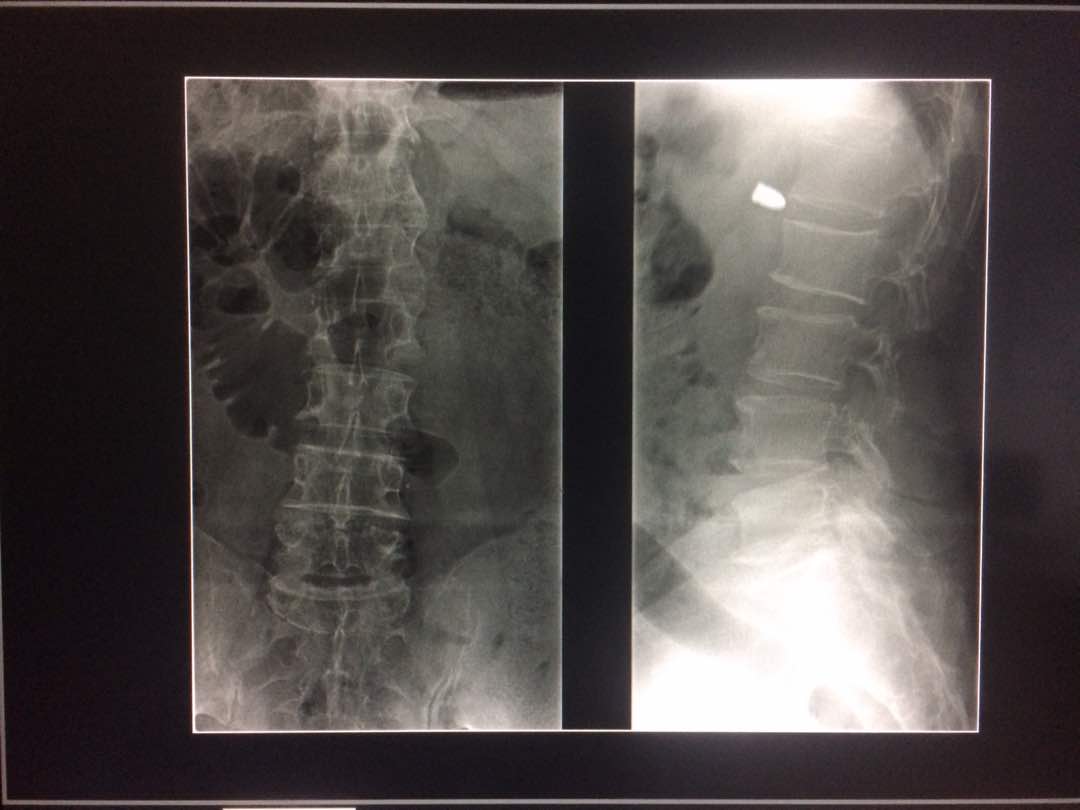

Diagnostico medico por Imagen